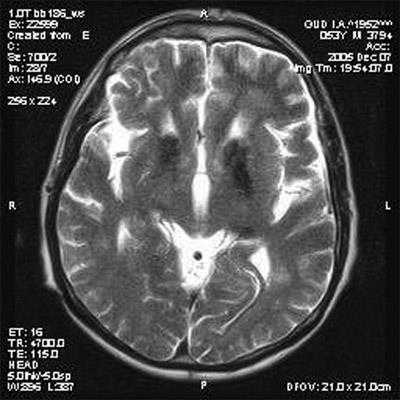

· МРТ головного мозга: более информативно в диагностике, чем КТ головного мозга. Характерны билатеральные очаги пониженной плотности 3-15 мм в диаметре в области базальных ганглиев (хвостатое ядро, скорлупа и бледный шар), в таламусе, в области зубчатых ядер и коры мозжечка - симптом «морды гигантской панды» [19]. По мере прогрессирования процесса выявляются признаки диффузного атрофического процесса головного мозга с равномерным расширением субарахноидальных пространств и желудочковой системы [20]. Изменения МР-сигнала от структур головного мозга могут отсутствовать у 7-17% детей со смешанной формой болезни Вильсона при наличии неврологической симптоматики в виде тремора, дизартрии и изменения мышечного тонуса по экстрапирамидному типу 5.

Проявления указанной патологии на МРТ выявляются благодаря повышению МР-сигнала в режиме Т2 и снижении в режиме Т1 от подкорковой области (ограды, скорлупы, хвостатых ядер, латеральных бледных шаров, наружной капсулы), среднего мозга, зубчатых ядер мозжечка и червя.

Первыми, как правило, поражаются скорлупа и хвостатые ядра. В мосту мозга распознаются поражение его срединных и дорзальных отделов с сохранностью пирамидных трактов и аналогичным изменением МР-сигнала от этих структур.

Последовательная эволюция изменений сигнала от дорзальной части моста напоминает «морду детеныша панды» с «глазами», которые формируются патологическим сигналом от центральных покрышечных проводящих путей.

Поражение среднего мозга носит диффузный характер, однако преобладает поражение белого вещества с сохранностью ядерных структур, в том числе наиболее крупных красных шаров. На поздних стадиях болезни выявляются атрофические изменения в подкорковых структурах.